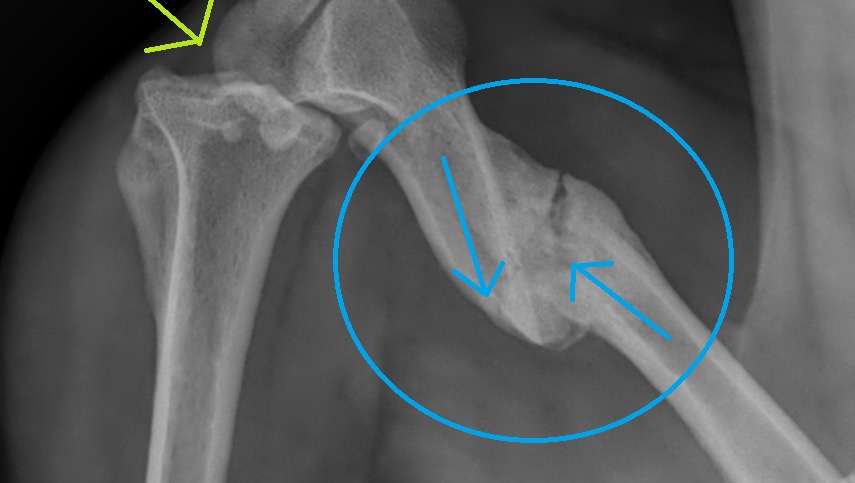

After the first day at our home, I noticed that she had a little bit of a limp and would sometimes lift one of her hind legs. We took her to the animal hospital that the rescue is connected with, and they took x-rays. The x-ray showed that she had a previous injury in her left hind leg, and it was a broken femur... a compound break. Also, the ball and socket showed trauma too. The femur showed signs of some healing, although the bones were not aligned. The theory is that she may have been hit by a car at one point. As a stray, she was living on the streets and somehow survived even with a broken leg.

We want what is best for Willow and what will give her the best quality of life. She definitely deserves a second chance. Because this is a pre-existing condition/injury, it will not be covered under any pet insurance. An orthopedic surgeon has been contacted by our vet’s office, and one of two possibilities would take place: see if her leg can be repaired and do an FHO procedure or, if the damage is too bad, amputate her leg. Either way, she is clearly a fighter, and I don’t think being a tripod dog would alter her sweet disposition. But, either procedure may cost between $3,500 to possibly $5,000, which is something my sister and I, newly retired seniors, were not prepared for. We will get this done for Willow because she deserves the best life. And we will dig into our retirement accounts to do it, but if anyone can help us just a little bit, it would be so greatly appreciated.

Willow’s broken femur